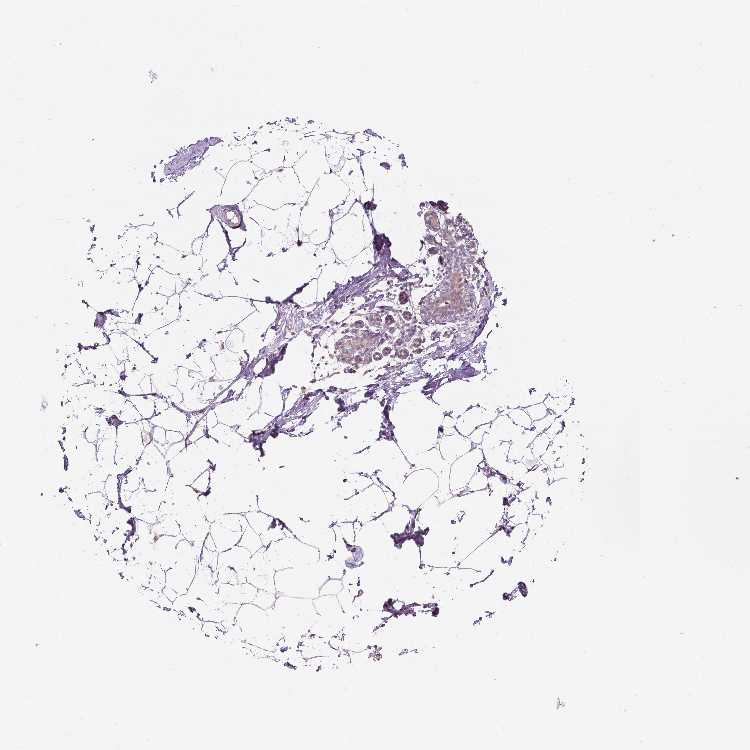

BREAST - Antibody stainingi

Antibody staining in the annotated cell types in the current human tissue is reported as not detected, low, medium, or high, based on conventional immunohistochemistry profiling in selected tissues. This score is based on the combination of the staining intensity and fraction of stained cells.

Each image is clickable and will lead to virtual microscopy that enables deeper exploration of all samples and also displays staining intensity scores, fraction scores and subcellular localization as well as patient and tissue information for each sample.

Antibody CAB019384

Adipocytes Medium

Glandular cells Low

Myoepithelial cells Low